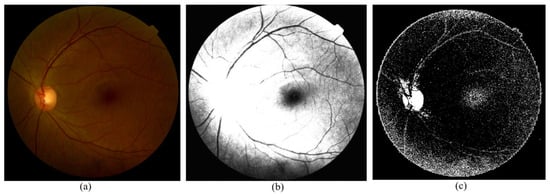

The preprocessed image is depicted in Figure 6. The APTOS-DDR combined data are employed for training and validating the model. For training, 70% of the data are used, and 15% for validation. The CNN layers extract the features, and the fully connected layers classify the data according to the class labels provided.

Figure 6. The original and preprocessed image in the model: (a) raw image, (b) CLAHE preprocessed image, and (c) sample of approximation coefficients from DWT preprocessing.